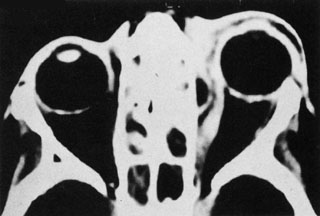

With preseptal inflammation, CT demonstrates soft tissue swelling of the eyelids and tissue adjacent to the orbital septum (Fig. 15). The orbit is not involved, and usually the sinuses do not show evidence of inflammation. The distinction between inflammatory preseptal cellulitis and edema cannot be made.63

Fig. 15. Computed tomography showing preseptal cellulitis of left eye. Note that all swelling is anterior to the orbital septum.